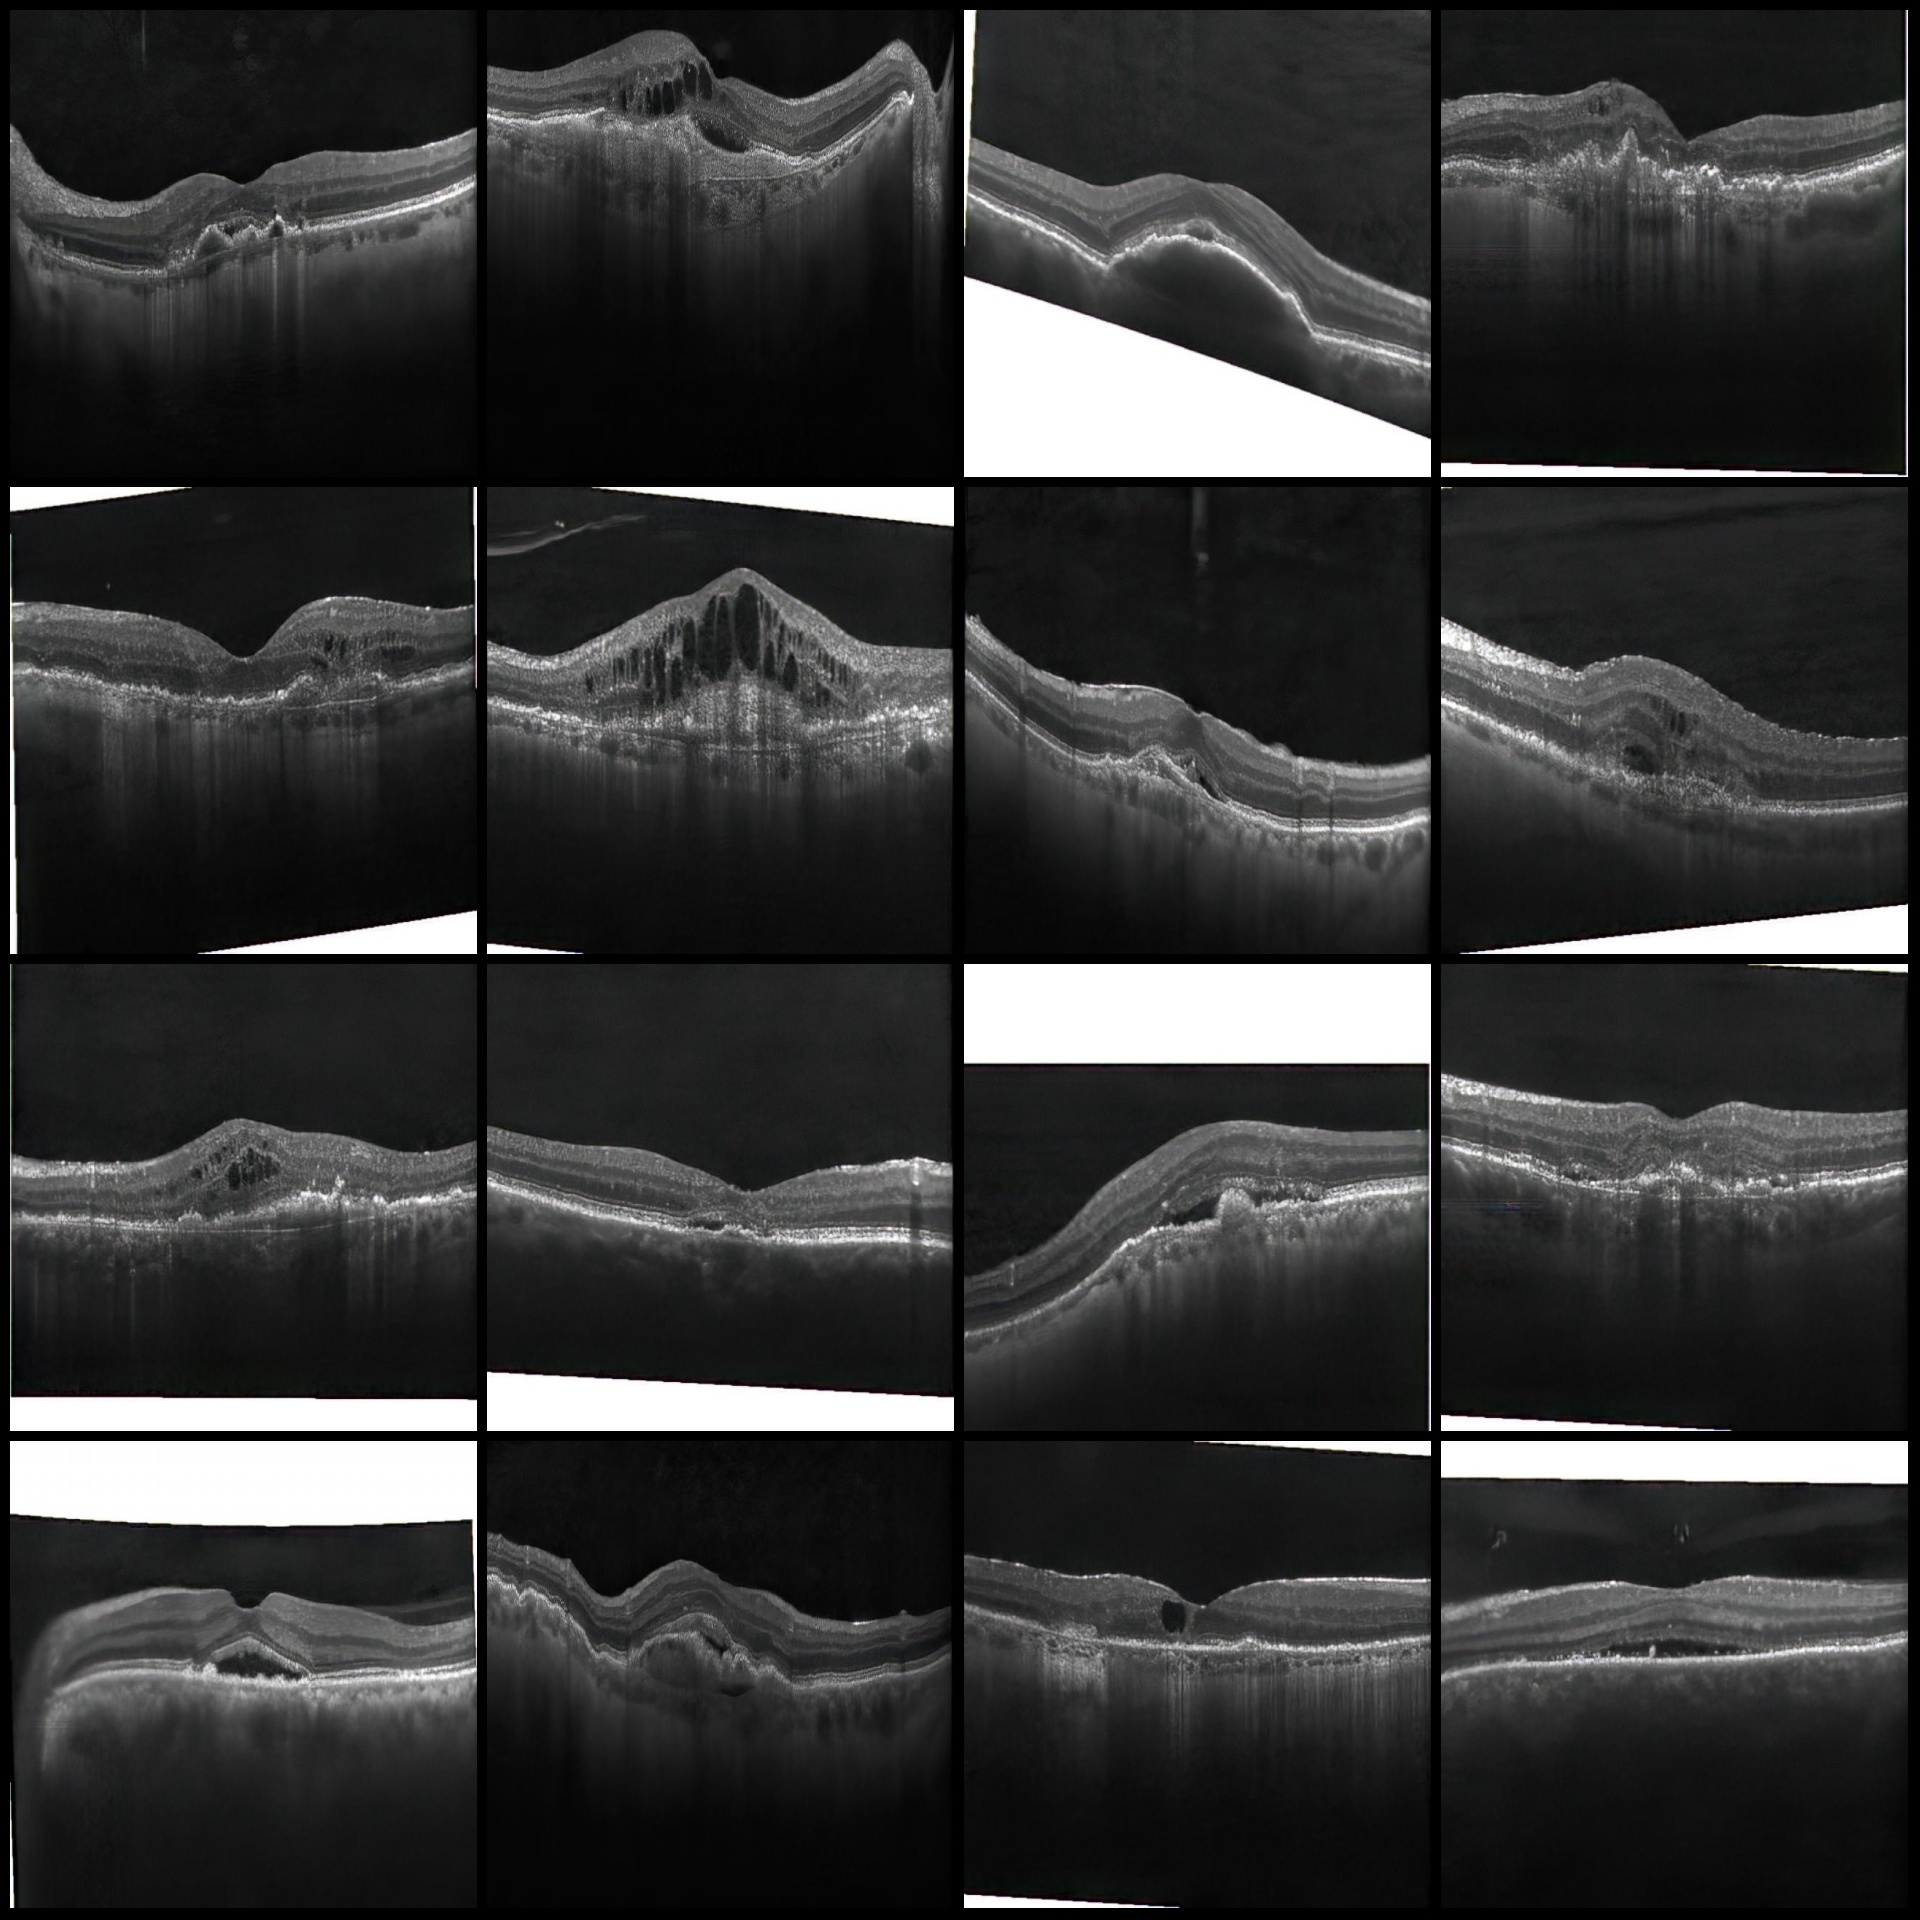

图片预览:

原图(随机选16张图):